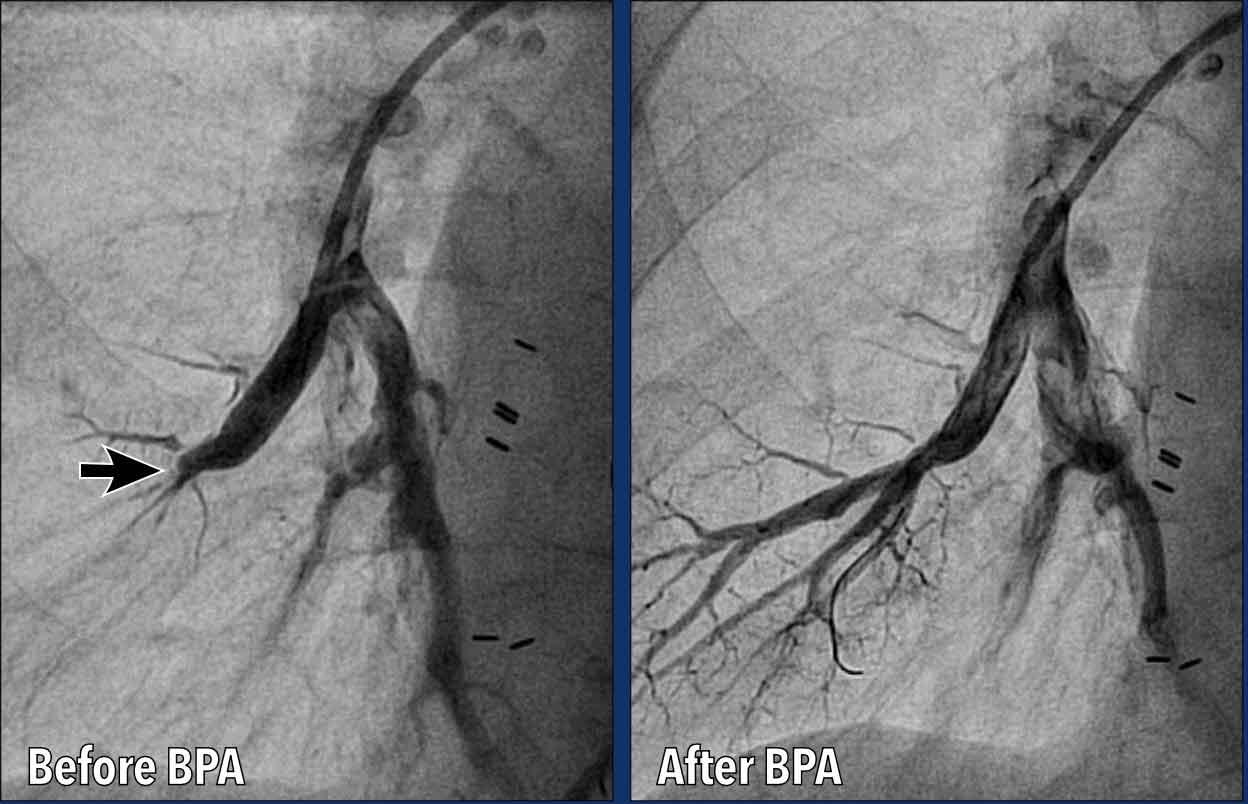

Tạo hình mạch phổi bằng bóng (BPA)

Tạo hình mạch phổi bằng bóng (BPA) là một thủ thuật can thiệp qua catheter được sử dụng để điều trị CTEPH.

BPA là một phương pháp thay thế ít xâm lấn so với phẫu thuật, dành cho các bệnh nhân:

- CTEPH không thể phẫu thuật (ví dụ: bệnh ở vị trí xa không tiếp cận được bằng phẫu thuật).

- Nguy cơ phẫu thuật cao.

- Tăng áp động mạch phổi tồn dư sau phẫu thuật nội mạc động mạch phổi (PEA).

Hình ảnh

Trước BPA có hình ảnh thuôn nhỏ cấp tính và tắc nghẽn động mạch phổi phân thùy đáy của thùy dưới phổi phải.

Sau BPA, động mạch thông thoáng, với lưu lượng máu được phục hồi vào các động mạch phân thùy.